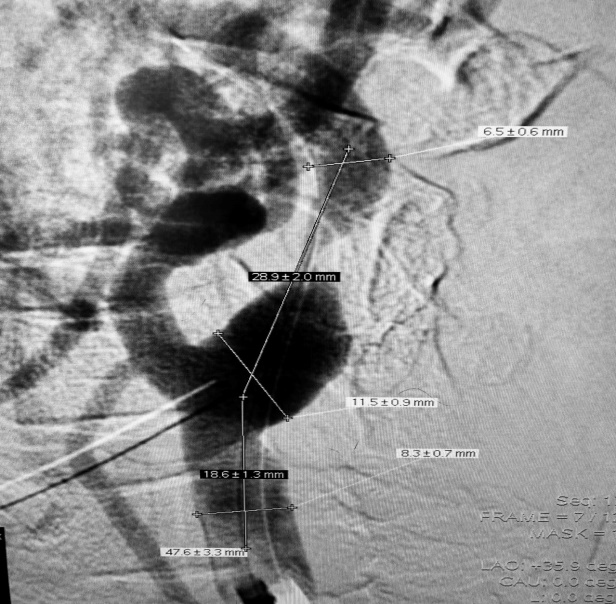

2022-10-11我院头颈DSA:

➤ 主动脉弓造影:Ⅰ型主动脉弓,右侧锁骨下动脉迂曲。

➤ 左侧颈内动脉造影:左侧颈内动脉C1段局限性狭窄约90%,C4-6段斑块形成,左侧大脑中动脉下干M2段狭窄约50%。